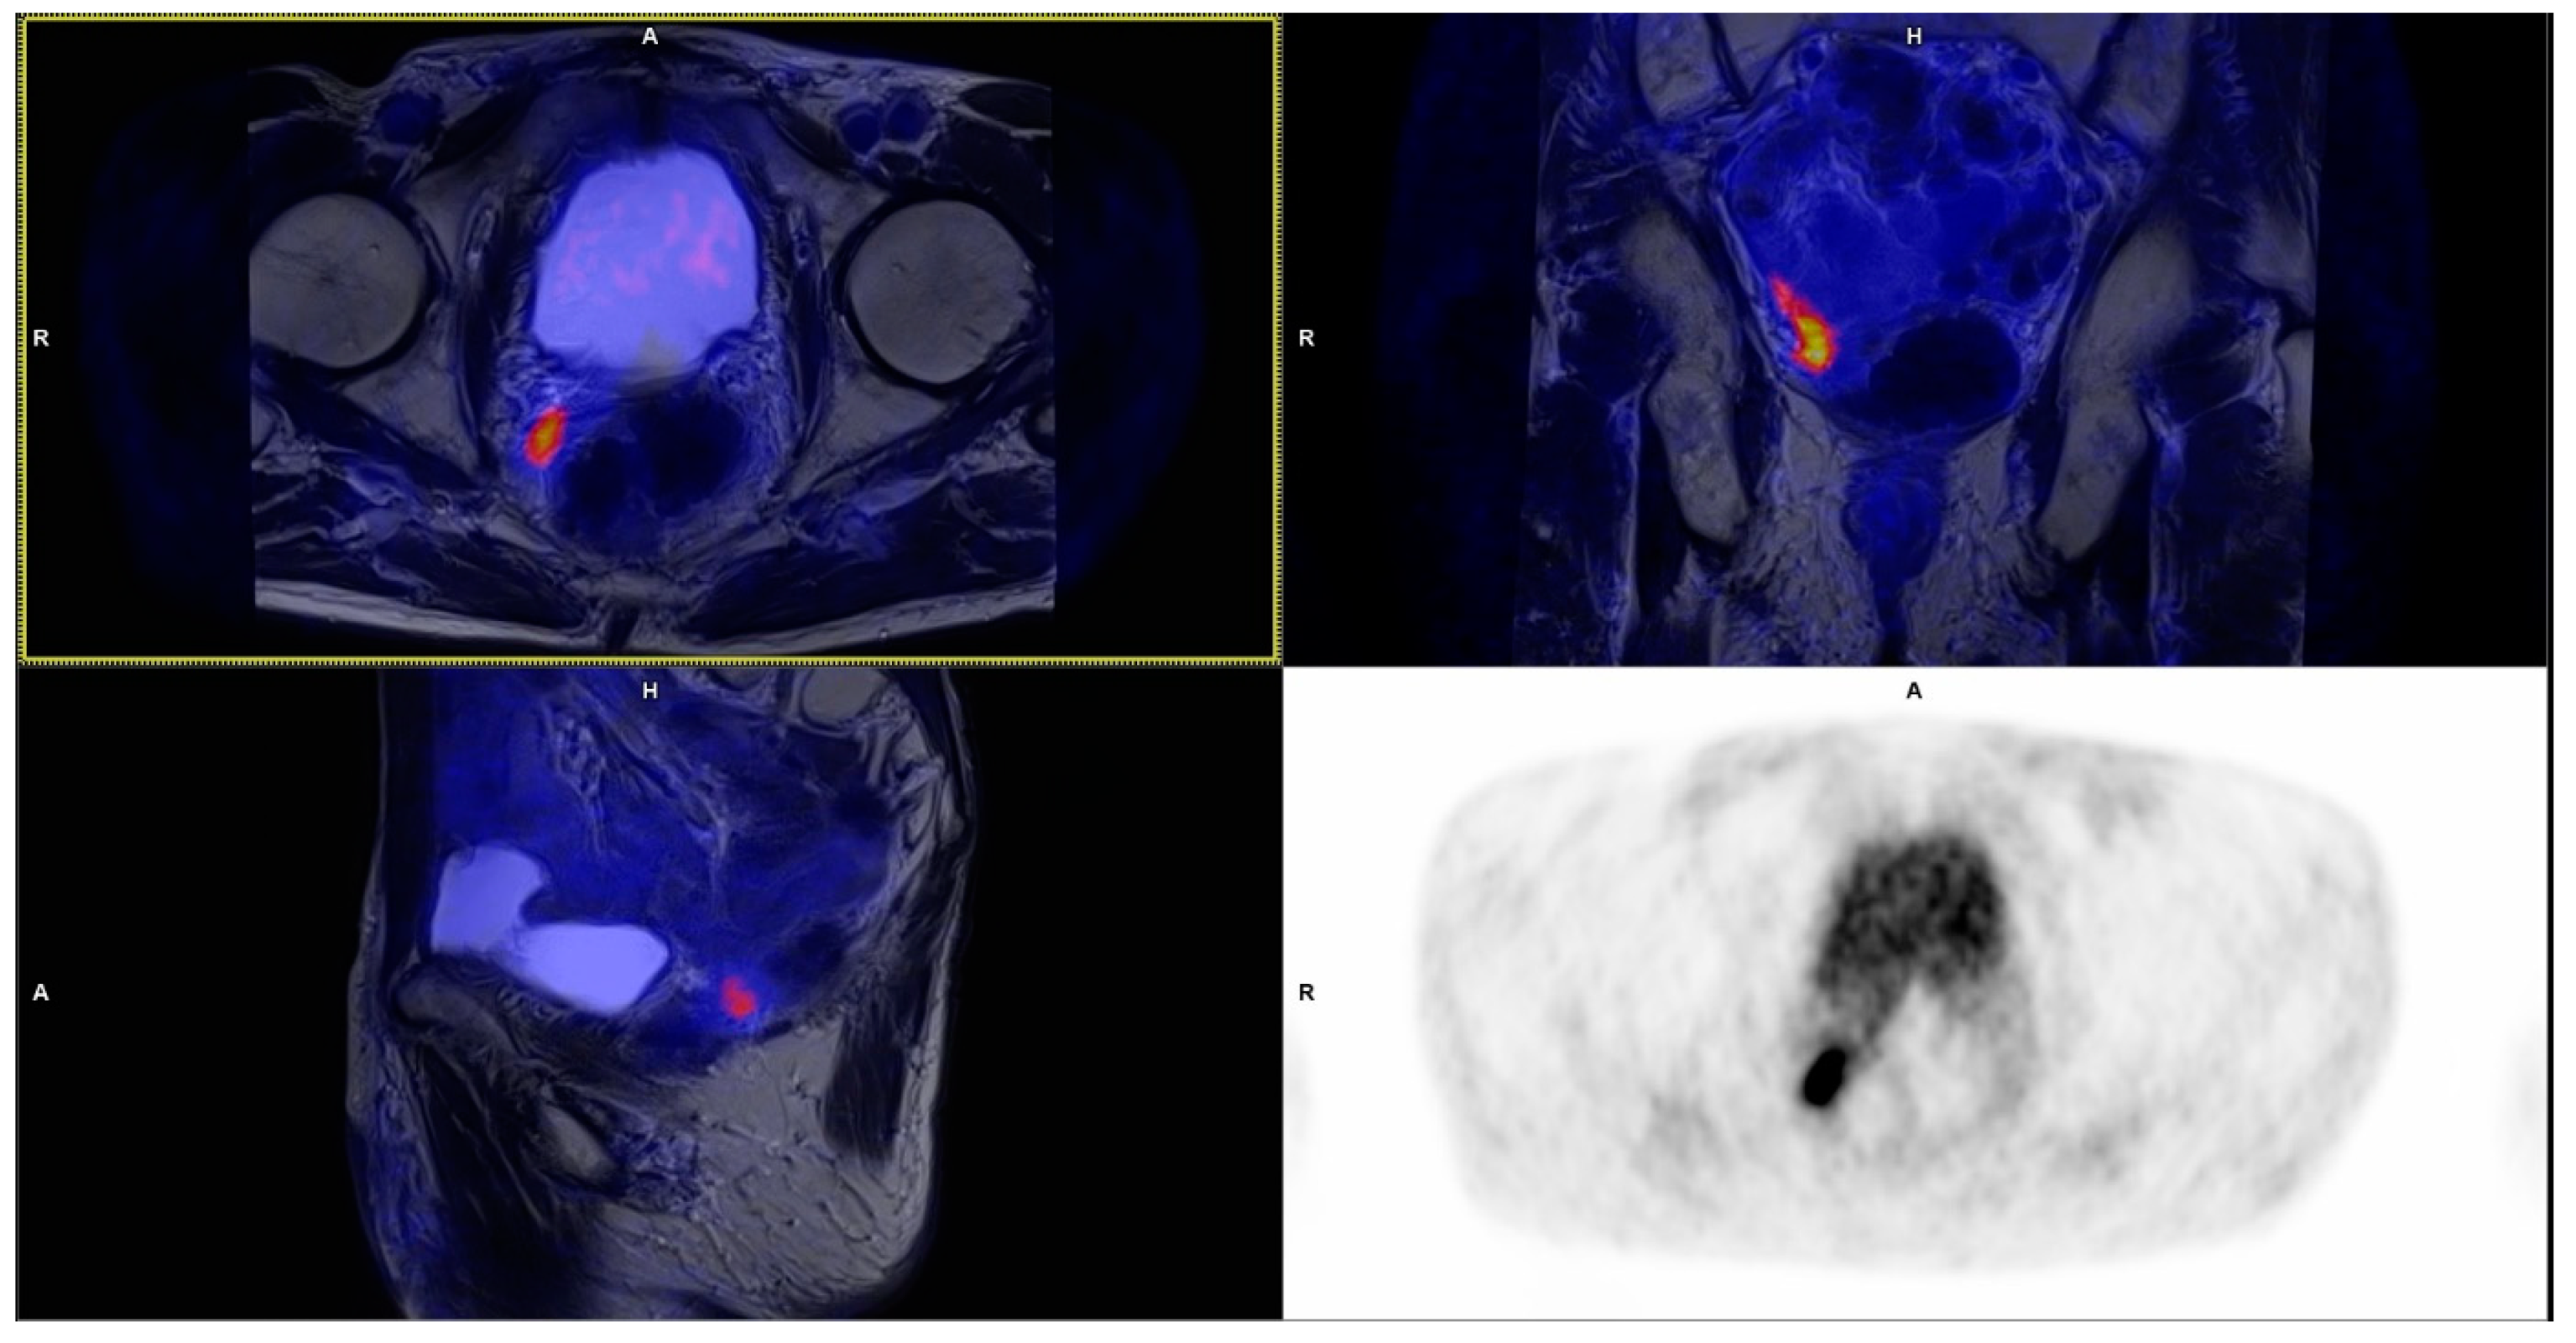

3.1. Local Recurrence

3.2. Lymph Nodes

3.3. Bone Metastases

| Recurrence Site | No. of Detected Lesions | Mean SUVmax ± SD | Size Range (mm) |

|---|---|---|---|

| Prostatic bed | 13 | 6.34 ± 2.53 | 6 × 4 up to 19 × 18 × 25 |

| Pelvic lymph nodes | 34 | 5.46 ± 3.28 | 3 × 3 up to 11 × 11 |

| Extrapelvic lymph nodes | 1 * | 3.75 | 3 × 3 |

| Bones | 5 | 4.75 ± 1.82 | 5 × 4 up to 8 × 8 |